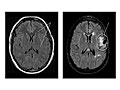

epilepsy have normal EEGs in between seizures. Imaging tests (MRI and CT)Magnetic resonance imaging (MRI) and

computed tomography (CT) are imaging tests that allow

a doctor to view the brain and evaluate the cause and location of

a possible source of epilepsy within the brain. The scans can reveal scar

tissue, tumors, or structural problems in the brain that may be the cause of

seizures or epilepsy. MRI is the more helpful test in most cases. Imaging tests

may not be done after a first seizure, but they are recommended in